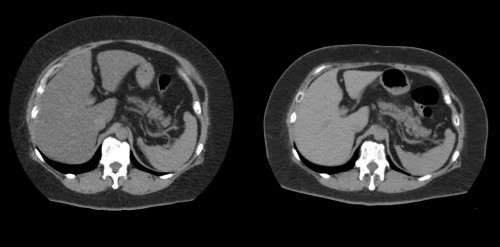

③

50代・男性(ご本人のご厚意で画像提供)

治療内容:チルゼパチド5.0mgの週1回自己注射による脂肪減少と脂肪肝改善

治療期間: 6ヶ月(26週)((用量は2.5mgから開始し最大で15mg。減量効果が得られる必要用量には個人差があります。))

費用:自由診療の場合は7700円(税込)×26(週)=200200円

想定されるリスク・副作用:下記に副作用を記載

※医療広告ガイドラインに準拠して表記

1:脂肪の減少

皮下脂肪の減少(赤色部分)